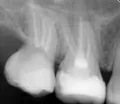

За день до события ел довольно твердые орехи, миндаль, 1 штуку (потом решил запить водой), но после них вечером и утром ел салаты, как обычно, и все нормально. После того как утром ел тонкий бездрожжевой армянский лаваш, который за 1 день стал немного черствым (корочка чуть тверже чем чипсы), в момент надкусывания дальними зубами услышал хруст и совсем небольшой кусочек зуба обнаружил в еде. По не понятной пока причине появилась трещина стенки 7-го зуба со стороны языка в четверти стенки, которая ближе к горлу. Видно, что есть трещина и в месте трещины есть небольшое углубление цвета кофейного налета (предположительно оттуда и выпал кусочек).

Стеночка еще держится, но упирается в десну и шатается.

Стенку зуба, конечно, необходимо только удалить, а восстановить коронковую часть зуба теперь можно будет только вкладкой и коронкой.